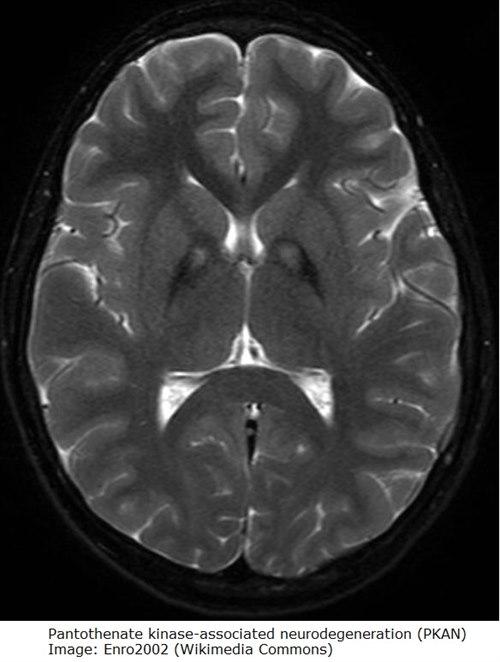

Klinisk bilde og avvik i erytrocyttenes form kan gi mistanke om sykdommen, MR kan vise relativt karakteristiske forandinger. Diagnosen stilles ved gentest som påviser PANK2-mutasjon

Illustrasjoner

Bilder